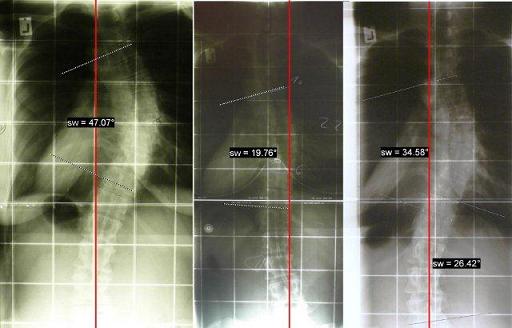

1. Um zu sehen, wie sich meine Wirbelsäule im letzten Jahr durch konsequentes Korsett-Tragen verändert hat, wurde ich nach 72 Stunden ohne Korsett geröntgt. Das Ergebnis ist superklasse!

Die Rotation hat sich deutlich gebessert, die Rippen stehen besser und meine Krümmung ist unter 40°. Da soll noch jemand sagen, dass eine Korsett-Therapie bei Erwachsenen nichts mehr bringt... Ich bin schmerzfrei, meine Optik hat sich deutlich verbessert und nun habe ich schwarz auf weiß (bzw. weiß auf schwarz), dass selbst radiologisch auch mit über 30 Jahren noch eine deutliche Korrektur möglich ist.

Hier zur Veranschaulichung mein Röntgenverlauf von Januar 2010 (links), über September 2010 (im Korsett) bis August 2011 (72h ohne Korsett).